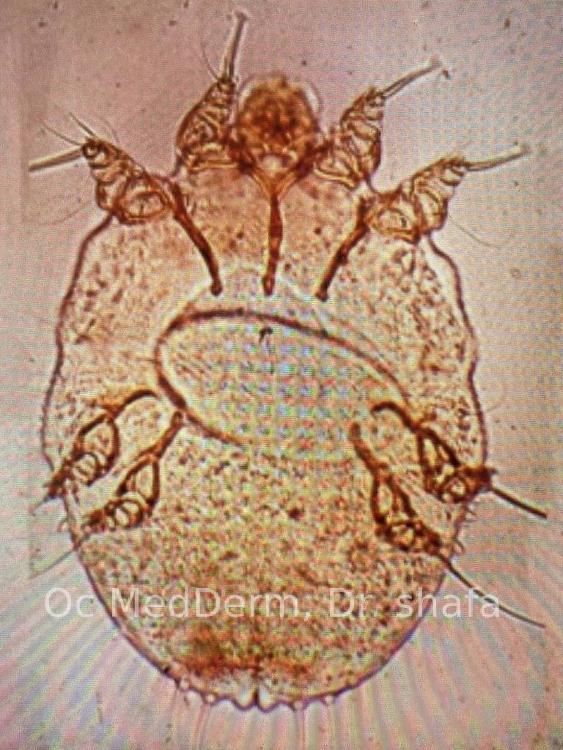

scabies mite